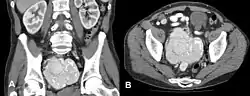

Choroba Castlemana (ang. Castleman's disease) – rzadkie schorzenie polegające na nienowotworowym rozroście komórek układu limfatycznego, do którego dochodzi w węzłach chłonnych lub poza nimi. Choroba Castlemana może być zlokalizowana (ang. unicentric Castleman's disease, UCD) lub wieloogniskowa (ang. multicentric Castleman's disease, MCD). Około 50% przypadków MCD spowodowanych jest przez herpeswirusy KSHV (ang. Kaposi's sarcoma-associated herpesvirus)[1], a w patofizjologii choroby odgrywa istotną rolę hipersekrecja IL-6.